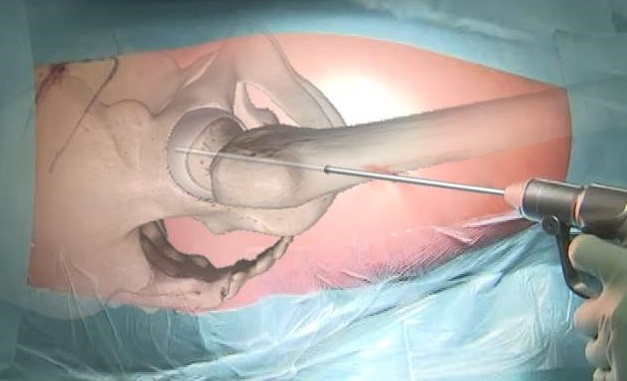

Il secondo tempo chirurgico è la procedura di core decompression con strumentario innovativo per la bonifica tridimensionale della lesione. Si esegue una piccola incisione di circa 1 cm distale al trocantere.

Sotto controllo scopico si infigge il filo di K attraverso il collo femorale fino all’area di necrosi.

Viene quindi eseguito un carotaggio di 9 mm di diametro e tramite tale accesso viene inserita una fresa manuale con una punta espandibile distale per rimuovere la lesione tridimensionale.

Infine il canale viene zaffato con un osso omologo arricchito dal concentrato cellulare midollare e PRF autologo preparato il giorno precedente l’intervento presso l’ematologia dell’istituto.